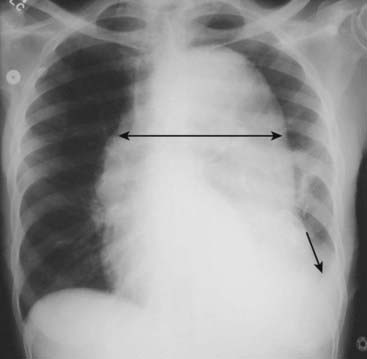

Recognizing Cardiomegaly in Infants

image Although this chapter focuses primarily on adult cardiac disease, in newborns and infants it is important to remember that the heart will normally appear larger relative to the size of the thorax than it does in adults. Whereas a cardiothoracic ratio greater than 50% is considered abnormal in adults, the cardiothoracic ratio may reach up to 65% in infants and still be normal because newborns cannot take as deep an inspiration as adults can and the relative proportions in the size of their abdomen to chest are not the same as for adults (Fig. 9-4).

image Any assessment of cardiac enlargement in an infant should take into account other factors such as the appearance of the pulmonary vasculature and any associated clinical signs or symptoms (e.g., a murmur, tachycardia, or cyanosis).

image

Figure 9-4 Normal infant chest.

In the normal infant, the cardiothoracic ratio may be as large as 65% (compared to 50% in adults) (double arrow). Any assessment of cardiac enlargement in an infant should also take into account other factors such as the appearance of the pulmonary vasculature and any associated clinical signs or symptoms (such as a murmur, tachycardia, or cyanosis).